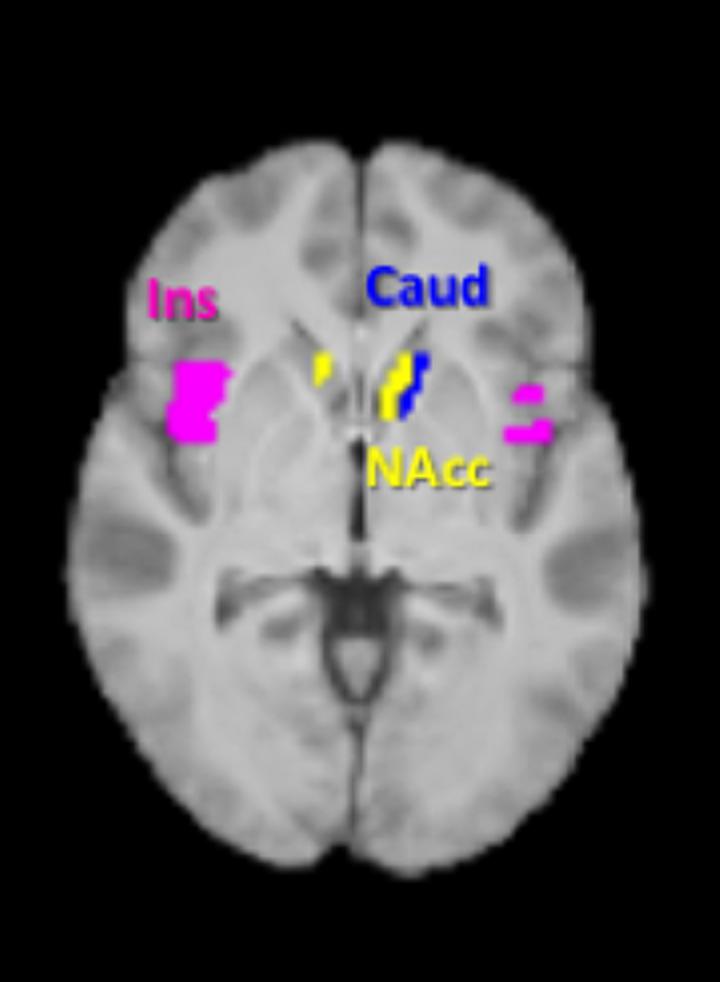

The team found that when volunteers drank the milkshake containing inulin-propionate ester, they had less activity in areas of their brain linked to reward -- but only when looking at the high calorie foods. These areas, called the caudate and the nucleus accumbens, found in the centre of the brain, have previously been linked to food cravings and the motivation to want a food.